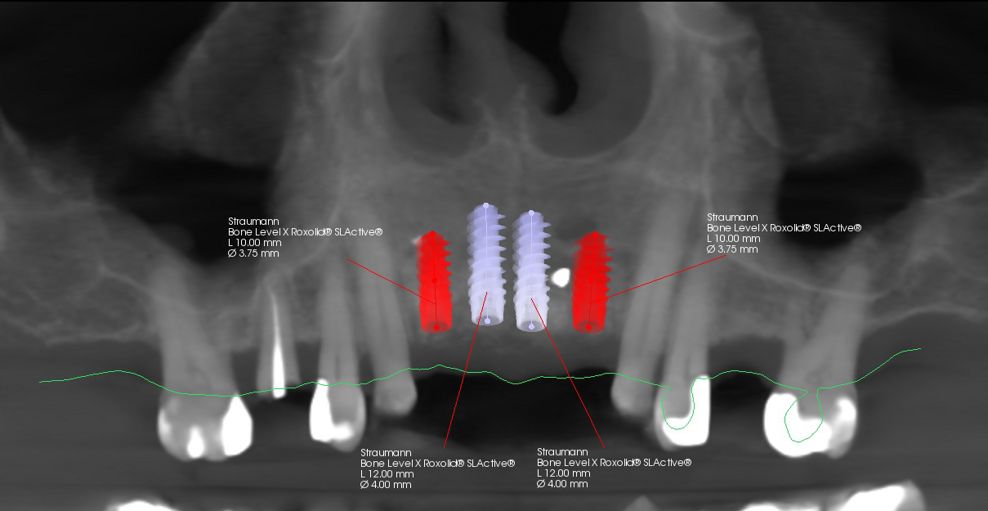

During the implant planning phase, we created a preliminary plan using 3D imaging software with a prosthetically driven implant planning approach (Figs. 9 & 10), and the plan was exported into surgical guide planning software for final planning and construction of the surgical drilling guide (Figs. 11a–c). The implants were planned in all four positions with the object of identifying the two most optimal and accessible sites for the placement of two implants and the corresponding bridge restoration.

After completion of the planning and drilling reconstruction, the surgical guide was 3D-printed with a Stratasys printer using MED610 resin (Stratasys). The two implants (4.1 × 12.0 mm Straumann Bone Level Tapered, Regular CrossFit, SLActive, Roxolid) were then placed utilising the Straumann guided surgery kit for precise guidance. The remaining piece of amalgam in the bone of tooth #21 was carefully removed—only a small piece in the gingiva remained (Fig. 12). The buccal bone was again thickened with EthOss, and the wound was closed with a semi-submerged technique, facilitating proper healing and integration of the implants (Figs. 13a & b).

Fig. 10: Final planning for two implants with merged intra-oral scan and CBCT data.